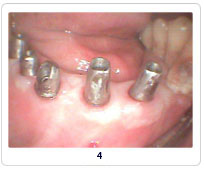

Implant Cases

Case 1   Case 2   Case 3   Case 4   Case 5   Case 6   Case 7   Case 8

Pictures Before And After Dental Implant India,Dental Implant Methods India,Types Of Materials Dental Implant Chennai India,X-ray Dental Surgery Goa India,Replacement Of Damaged Teeth Cochin India,Views Of Dental Treatment Procedure Delhi India,Dental Equipments Hyderabad India